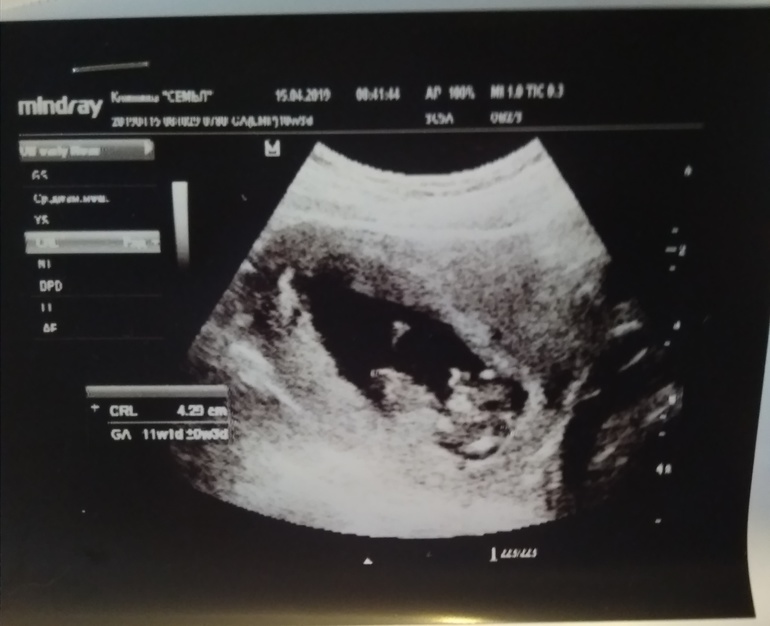

КТР 41мм, БПР 14мм. Прикрепился по задней стенке. СБ+, ДВ+. Видно было, как сердечко в груди бьётся 😍 Ручки, ножки, шейка - всё на месте, замерять не стали, просто глянули наличие. Ножки как лягушонок сложил наш пузожитель)) Излюбленная дочкина поза уже после рождения 😀